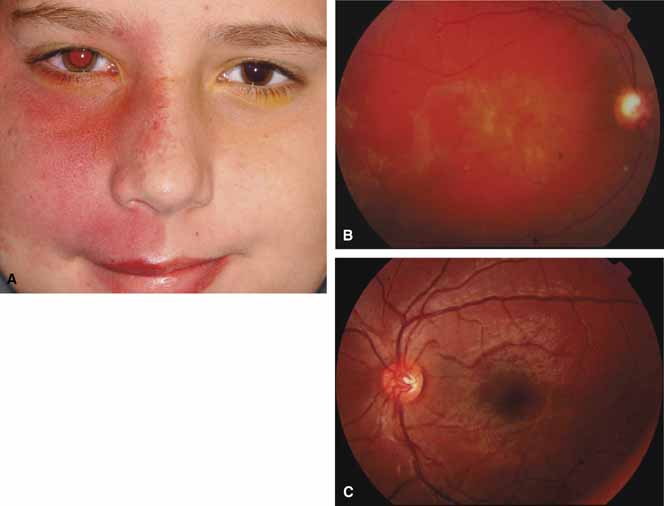

The possible association between retinitis pigmentosa and glaucoma dates back to 1862.11 Over the past century the reported glaucoma incidence has varied between 2.98% to 10% of all cases of retinitis pigmentosa.12,13 Of concern in all previous reports is the accuracy of the diagnosis of retinitis pigmentosa itself, a hereditary disease with diverse manifestations. Retinitis pigmentosa-like syndromes may mimic glaucomatous field loss, and the pattern of advancement of visual field loss in true retinitis pigmentosa may parallel that of typical open-angle glaucoma. Patients with undiagnosed retinitis pigmentosa may have subtle fundus findings, especially those with the sine pigmento form (Fig. 1). A clue to diagnosis is the disproportionate peripheral field loss in comparison to the degree of optic nerve cupping and rim pallor. Patients with atypical field loss and minimal optic nerve cupping should have an electroretinogram to exclude unsuspected retinitis pigmentosa.

Active retinal involvement in acute toxoplasmosis may be associated with an acute elevation of intraocular pressure, sometimes producing corneal edema. When the cornea is cleared with topical glycerin, the angle is found to be open and a minimal anterior chamber reaction is present. The mechanism of the glaucoma is believed to be immune complex (antigen–antibody) deposition in the trabecular meshwork, rather than obstruction by cellular debris.21 The elevated pressure responds well to timolol or acetazolamide and does not require topical corticosteroids. Systemic treatment of the active retinitis should follow only if the optic nerve (positive Marcus Gunn), macular center, or peripapillary retina is involved. This unique entity will be missed if a fundus examination is not performed in all cases of hypertensive uveitis (Fig. 2).

The majority of cases of ghost cell glaucoma occur following vitrectomy for diabetic retinopathy, vitreous hemorrhage due to trauma, or vitreous hemorrhage following anterior segment surgery (i.e., cataract extraction or corneal transplant). Although studies suggest that a disruption of the anterior hyaloid face may be a necessary precedent, ghost cell glaucoma probably can occur with an intact hyaloid if a sufficient quantity of vitreous blood is present.27 The clinical presentation includes acute pressure elevation, corneal edema, and lack of keratic precipitates. Minute tan cells (ghost cells) may layer out, producing a pseudohypopyon or, if admixed with blood, a “candy-striped” hypopyon. (Fig. 3) Intraocular pressure elevations after diabetic vitrectomy raise concerns regarding concomitant neovascular glaucoma. However, neovascular glaucoma rarely develops in the immediate postvitrectomy period, unless some anterior segment neovascularization was present preoperatively. Late-onset pressure elevations (> 6 to 8 weeks out) in a postvitrectomized diabetic eye usually signal neovascular glaucoma.